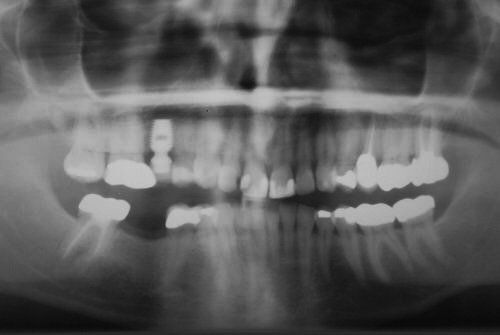

Unfortunately, it can be the case that a tooth (or teeth) are so badly damaged by trauma, bacteria, or tooth decay that removal is the only option. In this case, we recommend that a patient has dental implants inserted to replace any missing teeth. Modern dental implants are long lasting, strong, and look, feel, and function just like real teeth.

At the Dental Innovations clinic in Wasilla, AK, we specialize in single and multiple implant restorations. Our team can use a wide range of implant systems to provide patients with a full mouth of even, strong teeth. Contact our dental clinic today to arrange a consultation to discuss what dental implants may be the best for you.